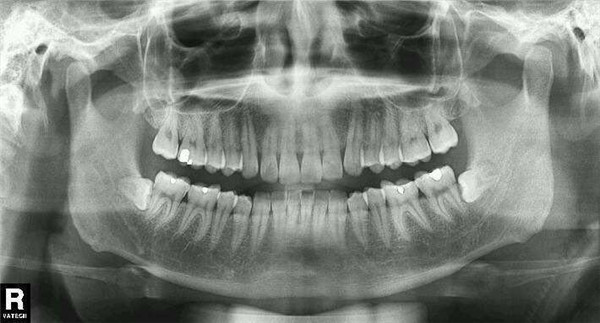

【幸福力微课】您的牙齿保健了吗?

三、牙疼的几种原因和根管治疗;

四、长了立事牙怎么办;

三、牙疼的几种原因和根管治疗

1、龋齿表现为刺激痛,即遇冷遇热疼痛,一般分为浅龋中龋和深龋,浅龋是仅牙齿表面的牙釉质受到损害,牙齿基本没有感觉或有轻微的酸痛。中龋是龋病已经进展到牙本质浅层,形成龋洞,病人对冷热酸甜等刺激比较敏感,尤其对冷刺激更为敏感,常常是用冷水刷牙时会感觉不舒服或者疼痛。深龋是龋病已经进展到牙本质深层,形成很深的龋洞,病人会感觉对冷热刺激敏感,疼痛也比中龋剧烈。

2、如果龋齿没有的得到及时的治疗,就会侵及牙神经,发展成牙髓炎,髓腔内的炎性渗出物无法得到彻底引流,导致局部组织压力增高,使感染容易很快扩散到全部牙髓,并压迫神经产生剧烈的疼痛。

3、急性牙髓炎没有及时治疗,炎症继续向下发展,可能会导致牙根尖周围组织发炎,急性发作时也会导致剧烈疼痛。急性牙髓炎和根尖周炎的病人通常会说牙疼的时候半个脑袋都疼,晚上不能入睡,饭也吃不下,就是俗话说的“牙疼不算病,疼起来真要命”,这时来就医,就需要做根管治疗了。

4、根管治疗俗称“杀神经”治疗,就是医生将牙齿内的病变牙髓组织清除,在根管内封药消炎,并将根管扩大清洁,然后用牙胶将根管充满,最后再把牙补好。这种方法是治疗牙髓病的首选方法,通常至少要来三次,7至10天左右来一次,虽然有点麻烦,但这是能把牙根留住的最好方法。

四、长了“立事牙”怎么办?

有的朋友会问长了“立事牙”怎么办?立事牙是我们对智齿或第三磨牙的俗称,一般在18岁以后开始萌出。由于人类进化的原因,这颗牙经常没有足够的空间萌出,因而会形成错位阻生。萌出过程中的智齿被牙龈瓣覆盖形成一个盲袋,食物残渣容易聚集在此处难以清洁,因而常常会反复发炎,形成急性智齿冠周炎。这样的患者在刚开始发现牙疼或者肿了的时候,就口服抗生素,这样可以避免疾病拖严重了,比较重的时候可能会出现张口受限,半边脸肿胀、吞咽时嗓子疼,有时会伴有发热。所以尽早吃抗生素缓解肿痛,很有必要。等到炎症消失了,尽早去医院拔除,避免以后再发生感染和肿痛。